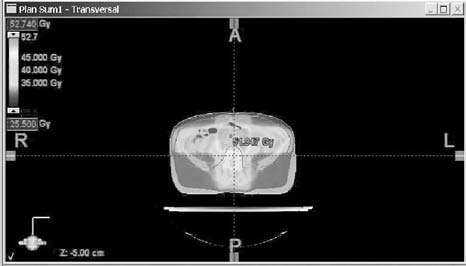

Obr. č. 1: Distribuce izodóz při abdominopelvickém

ozáření - technice „open field" v rovině transverzální, při

frontální a sagitální rekonstrukci, 3D